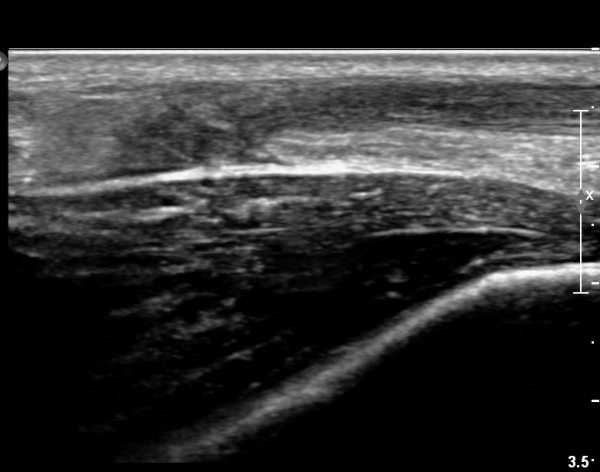

[¹ß¸ñ] simultaneosus tear of GCM and achiles tendon

abrupt leg pain developed during foot volleyball

he walk with severe limping with no weight bearing on rt. leg. on examination, there is local tendernes at GCM and achiles tendon, severe pain with ankle dorsiflexion.

ÃÊÀ½ÆÄ °Ë»ç

rec) short leg splint with crutch gait. he refused splint, then visit other hospital and took operation.